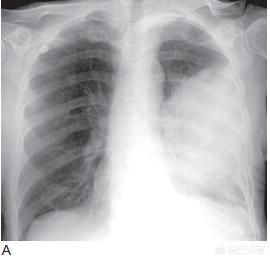

通常、嗄声は一定期間内あるいは一定期間の治療で自然に治ります。嗄声が出たり出なかったりを繰り返し、抗炎症治療を行っても治りにくい場合は、進行した肺癌が反回喉頭神経に腫瘍抑制作用を及ぼしていると考えられ、腫瘍の大きさや浸潤の深さ、増殖や転移の有無を明らかにするために、CTなどのX線検査などを受けることが勧められます。

肺癌患者の嗄声が改善の兆しがなく徐々に悪化する場合は、基本的に腫瘍が反回喉頭神経を圧迫または侵害することが原因であることが確実であり、胸部強調CTと喉頭鏡検査を行って状態を明らかにすることができる。喉頭鏡検査で声帯の麻痺が認められれば、反回喉頭神経が障害されていることは確実です。反回喉頭神経が圧迫されているだけであれば、手術で切り離すことができますが、悪性腫瘍による反回喉頭神経浸潤では手術の可能性はほとんどありません。中心性肺がんによる反回喉頭神経の浸潤や縦隔リンパ節による反回喉頭神経の圧迫は、腫瘍が進行していることを意味します。